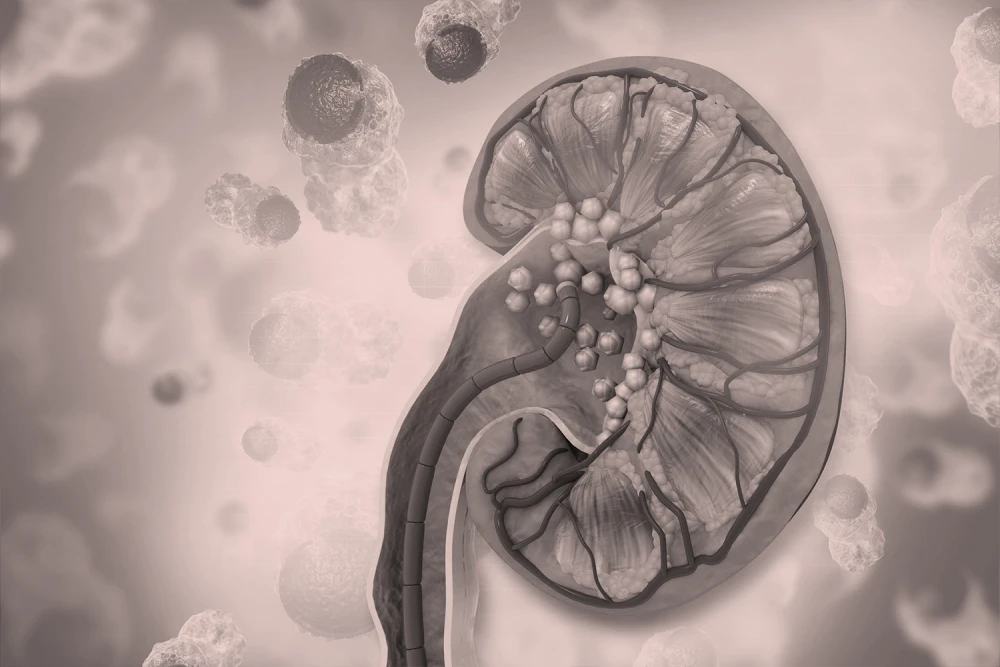

Kidney Stones & Stone Disease

Kidney and ureteric stones can be incredibly painful and disruptive of daily life appropriately managed, however, treatment can be targeted, safe, and less invasive than most imagine.

Symptoms may include sharp back or abdominal pain, blood in urine, frequent urination and sometimes nausea or vomiting.

Treatment options include medication, laser lithotripsy, and minimally invasive procedures — depending on the stone’s size & position.